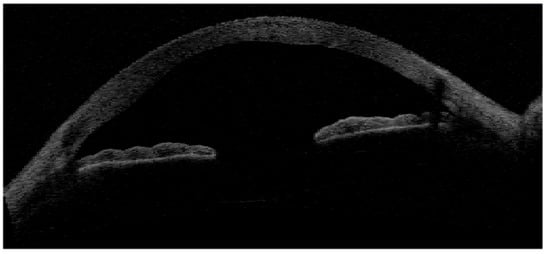

- Veres, A.; Tapasztó, B.; Kosina-Hagyó, K.; Somfai, G.M.; Németh, J. Imaging lid-parallel conjunctival folds with OCT and comparing its grading with the slit lamp classification in dry eye patients and normal subjects. Invest. Ophthalmol. Vis. Sci. 2011, 52, 2945–2951. [Google Scholar] [CrossRef] [PubMed][Green Version]

- Gumus, K.; Pflugfelder, S.C. Increasing prevalence and severity of conjunctivochalasis with aging detected by anterior segment optical coherence tomography. Am. J. Ophthalmol. 2013, 155, 238–242. [Google Scholar] [CrossRef] [PubMed]

- Qiu, W.; Zhang, M.; Xu, T.; Liu, Z.; Lv, H.; Wang, W.; Li, X. Evaluation of the effects of conjunctivochalasis excision on tear stability and contrast sensitivity. Sci. Rep. 2016, 6, 37570. [Google Scholar] [CrossRef] [PubMed]